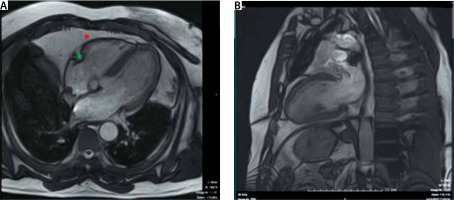

Cardiac magnetic resonance imaging

CMR allows volumetric EAT quantification with high reproducibility [10]. Different CMR imaging sequences can be used for EAT quantification (Figure 5). Contrary to CCT, CMR-acquired EAT estimation does not require patient radiation exposure. Assessment of EAT volume by CMR does not require gadolinium administration. For these reasons, CMR can be considered a safe technique to determine EAT volume if CMR contraindications are absent [98]. The drawbacks of CMR are the high cost, relatively long examination times, and limited availability. It should be emphasised that CMR has greater slice thicknesses than CCT, reducing EAT volume segmentation accuracy [9]. Furthermore, the depiction of the pericardium on the inferior CMR slices is more complex than on CCT axial images [9].

FIGURE 5

A 4-chamber view (Panel a) and 2-chamber view of the left ventricle from the cine views (SSFP sequence). Adipose tissue is bright in this imaging sequence. Note that it is more difficult to depict the pericardium on CMR compared to cardiac CT (see Figure 1). Note the EAT in the atrioventricular groove (green *) and pericardial outside the pericardium (red *)